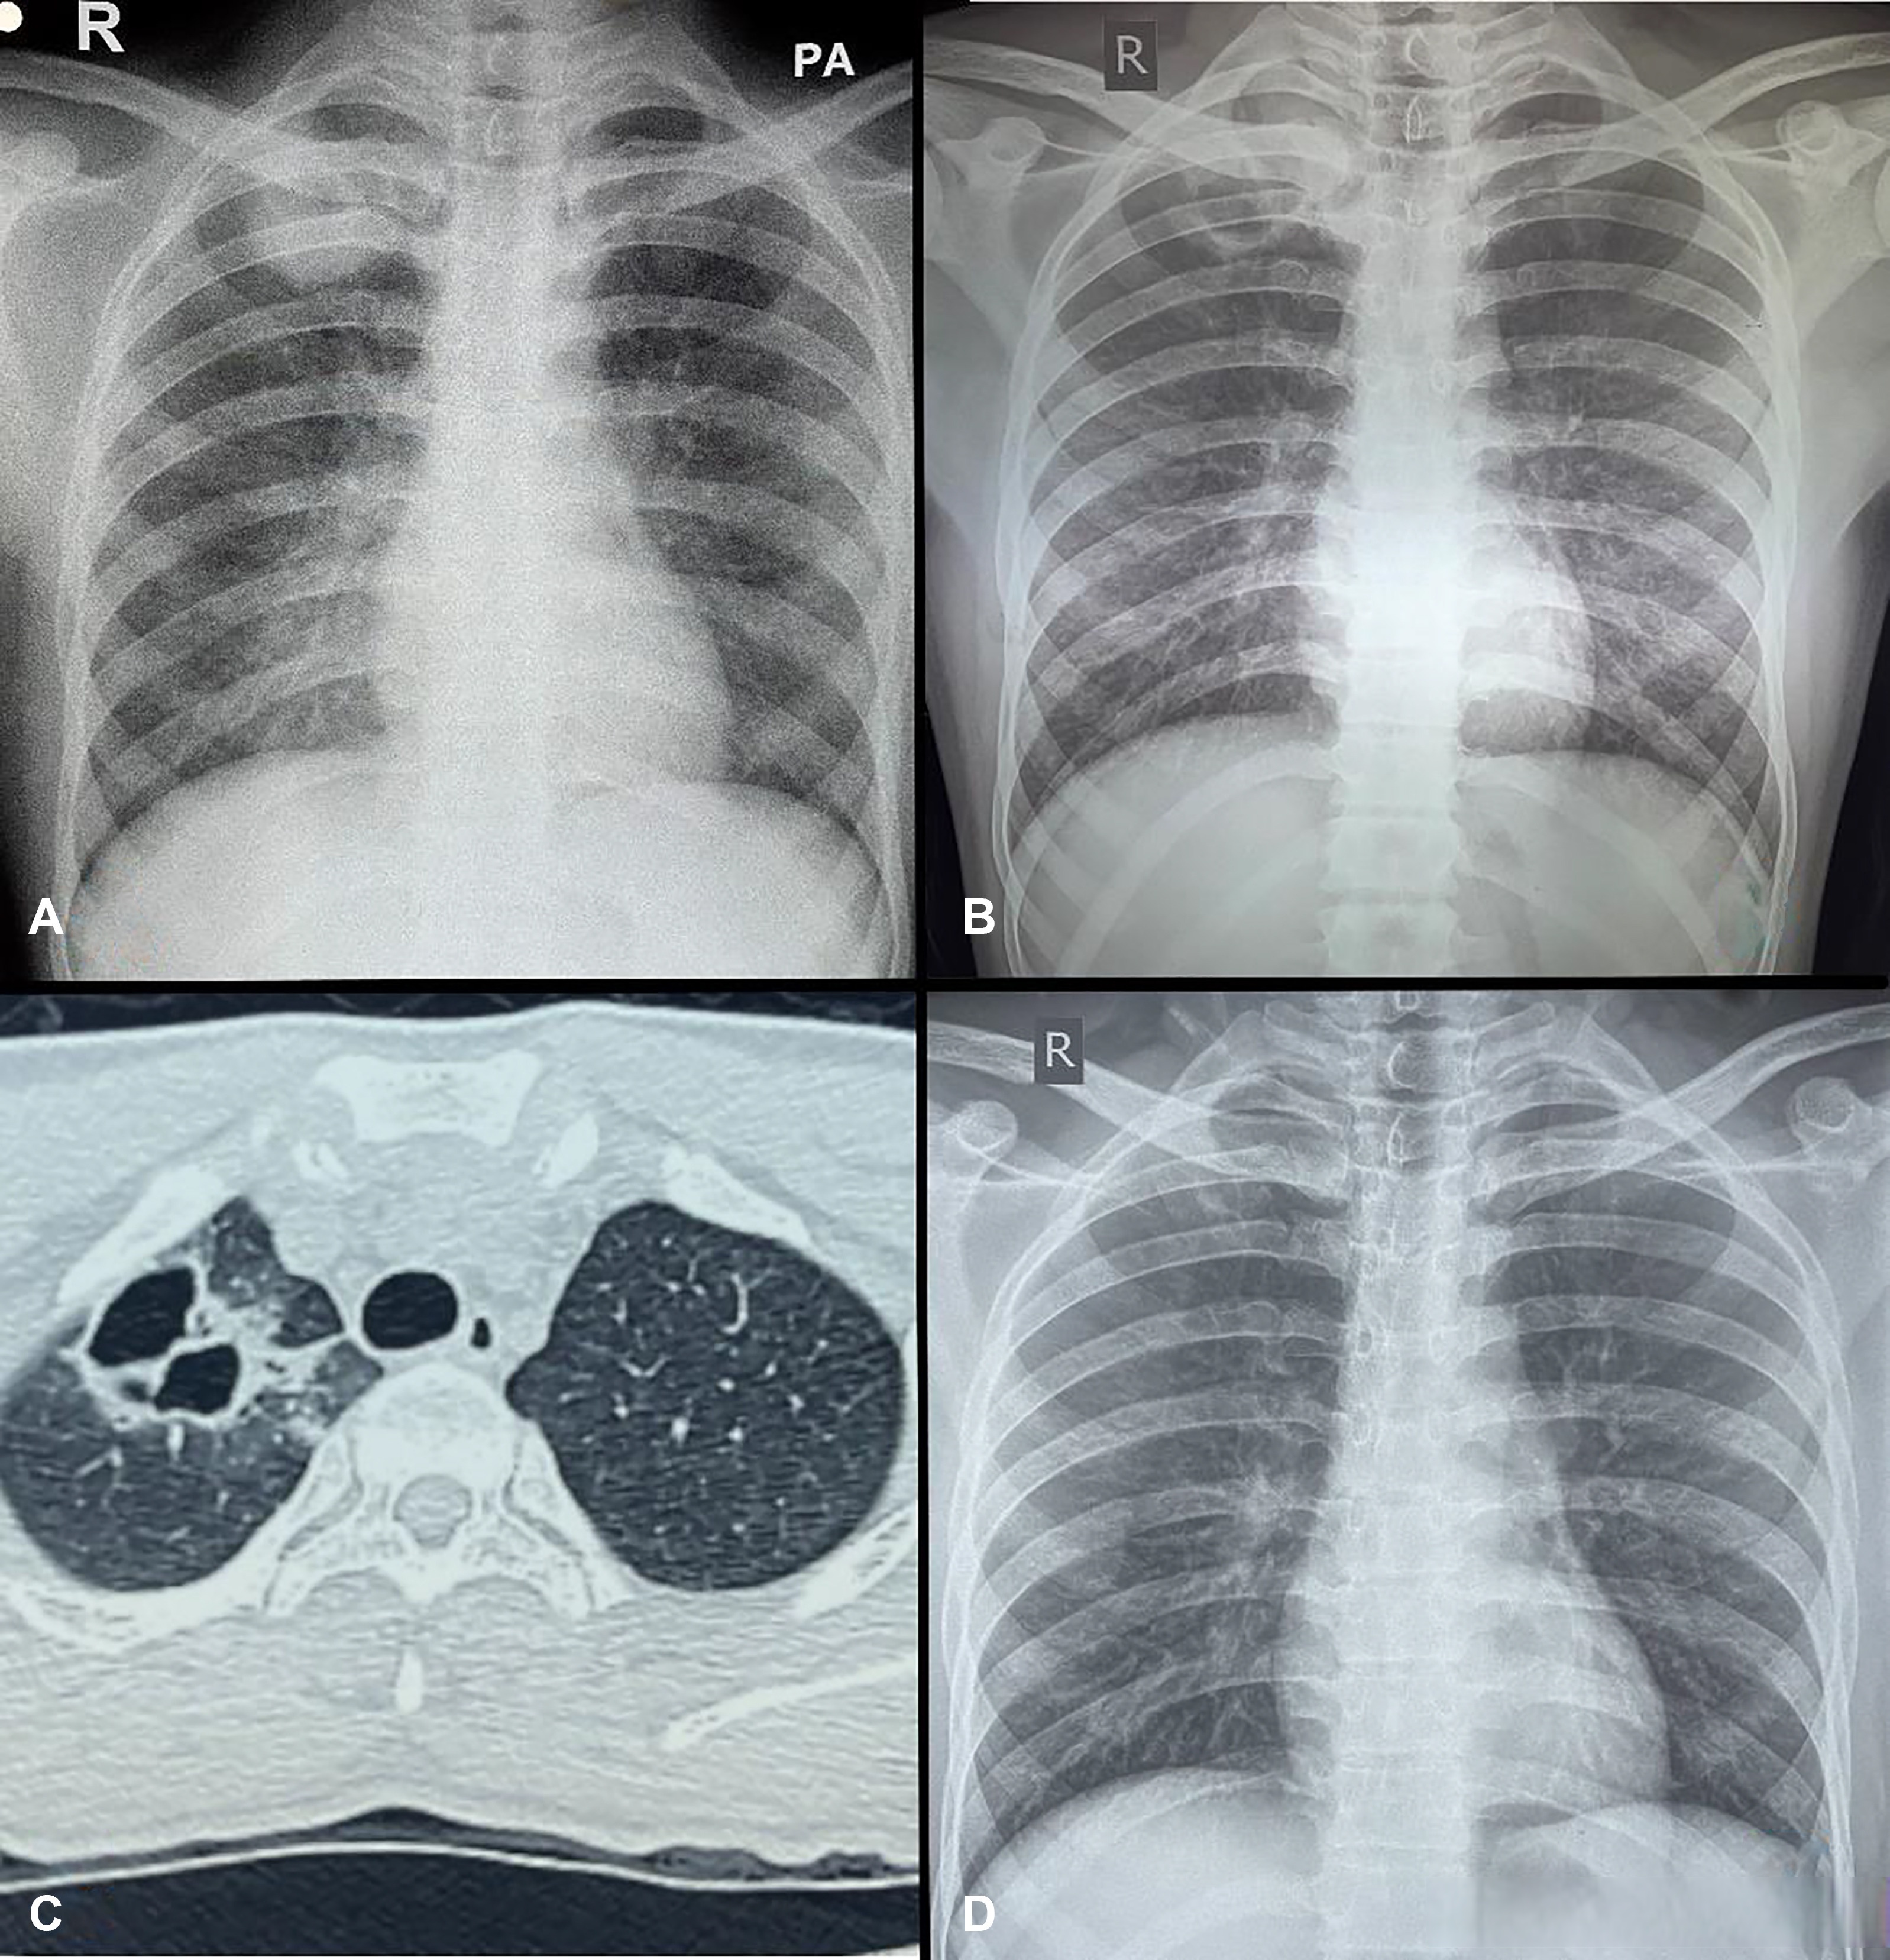

3、肺心病晚期症状主要包括呼吸衰竭相关症状心力衰竭相关症状以及其他系统受累症状呼吸衰竭相关症状肺心病晚期患者常出现严重呼吸衰竭,呼吸困难加重,夜间尤为明显,部分患者无法平卧,需端坐呼吸发绀是典型表现,因缺氧导致口唇甲床等部位呈青紫色精神神经症状突出,如神志恍惚谵妄躁动抽搐甚至。

4、肺心病晚期症状主要包括以下方面1呼吸系统症状显著加重患者常出现持续性胸闷气促及呼吸困难,活动耐量急剧下降,轻微体力活动如穿衣步行即可引发气喘,休息后缓解不明显这是由于肺动脉高压导致右心负荷过重,进而影响肺部气体交换功能,加重低氧血症所致2体循环淤血与水肿双下肢凹陷性水肿是。

5、肺心病晚期患者死前症状主要表现为重度心衰及其引发的多系统功能障碍,具体如下1 严重呼吸系统症状患者会出现持续性呼吸困难,尤其在活动或夜间平卧时加重,表现为端坐呼吸需坐起或半卧位才能缓解憋喘和阵发性夜间呼吸困难夜间突然因缺氧惊醒,需立即坐起口唇及甲床紫绀发绀会显著加重。

6、肺心病后期的症状主要包括以下几方面一呼吸系统症状持续加重肺心病后期患者最突出的表现是呼吸困难逐渐加重,初期可能仅在活动后出现,后期静息状态下也可能发生患者常伴随喘息气急,甚至因缺氧导致口唇指甲发绀青紫咳嗽咳痰症状可能因肺部感染加重而频繁出现,痰液性状可能从白色黏液转为脓。

11、肺心病晚期患者的临床表现主要包括以下几个方面1心肺功能衰竭患者心肺功能严重受损,表现为持续性呼吸困难喘息加重心悸胸闷,活动后症状显著加剧心力衰竭是晚期典型特征,可出现下肢水肿肝脾肿大腹水等体征,严重者因右心衰竭导致全身循环淤血2神经系统症状肺性脑病是晚期常见并发症,因二氧化碳潴留和缺氧引发脑功能障碍。

13、肺心病后期主要出现呼吸功能失代偿和心脏功能失代偿两类症状,具体表现如下呼吸功能失代偿患者会出现明显的胸闷气喘症状,呼吸频率加快且呼吸深度变浅,需依赖持续吸氧才能维持基本呼吸功能若未及时供氧,可能因二氧化碳潴留导致呼吸性酸中毒,表现为意识模糊嗜睡甚至昏迷此外,肺部感染风险显著增加。

14、呼吸衰竭相关症状肺心病后期患者常因肺部功能严重受损导致呼吸衰竭,核心表现为低氧血症与二氧化碳潴留低氧血症会引发全身组织缺氧,导致胸闷心悸发绀口唇或指甲青紫等典型症状二氧化碳潴留则刺激中枢神经系统,引发头痛多汗,并干扰睡眠节律,表现为夜间失眠日间嗜睡病情进一步加重时,患者可能。

15、肺心病晚期死前症状主要包括以下几类,具体表现因人而异1 心肺功能衰竭患者常出现呼吸困难呼吸急促,伴有明显紫绀口唇指甲发绀,提示氧气交换严重受损心脏因长期超负荷运转,可能出现心跳加速心律失常,甚至心源性休克这是由于肺部疾病导致通气功能下降,心脏无法有效泵血,最终引发多器官。